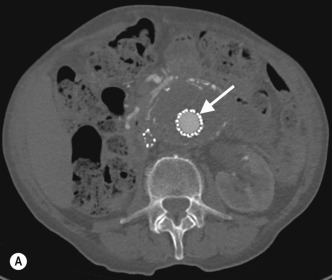

Anatomical mapping of thoracic or abdominal coarctation are well performed by both CT and MR, although by using phase-contrast techniques both the extent of collateral flow and peak velocities (V) through the area of maximum stenosis can be measured with MRI. The pressure gradient can then be estimated using a modified Bernoulli equation (Δ P = 4V 2 ) which can be useful for assessing change at follow-up ( Figs 77.4 and 77.5 ).

Fig. 77.5, Abdominal Coarctation in a Young Patient With Severe Hypertension and Chronic Mesenteric Ischaemia.